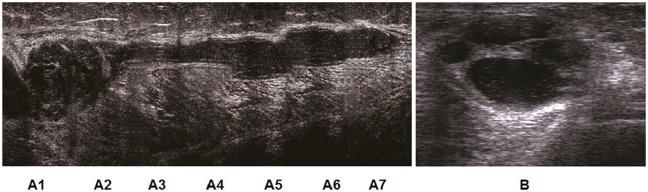

Single-center retrospective study that included 42 patients with knee joint disorder associated with ruptured BCs were treated by ultrasonographic guided aspiration of fluid from the cyst and different points from the calf then intra-lesional injection of corticosteroids once or twice, 1 week apart. Follow up were done weekly until complete resolution of symptoms. Visual analog scale (VAS) and Rauschning-Lindgren and Lysholm Knee Scoring Scales (RLC) were used for assessment.

Clinical parameters (VAS and RLC) improved significantly in all patients at both post injection evaluation visits (1 week and 12 weeks). Ultrasonographic features improved significantly with complete disappearance of free fluid in the calf in 35 (83.3%) cases 1 week after the injection, and in 41 (97.6%) after 12 weeks. As regards BCs only 4 (9.5%) cases showed complete disappearance after 1 week and there was recurrent BCs in 38 (90.5%) cases which required reaspiration. While after 12 weeks, BCs were completely disappeared in 23 (54.8%) cases, most of the relapsed BCs were complex BCs. No side effects were reported in all cases.

在两次注射后评估访视(1周和12周)时,所有患者的临床参数(VAS和RLC)均有显著改善。超声特征显著改善,注射后1周,35例(83.3%)小腿游离液体完全消失,12周后41例(97.6%)消失。仅就BCs而言,1周后仅4例(9.5%)完全消失,38例(90.5%)复发,需要再次抽吸。12周后,23例(54.8%)BCs完全消失,大多数复发的BCs为复杂性BCs。所有病例均未报告副作用。